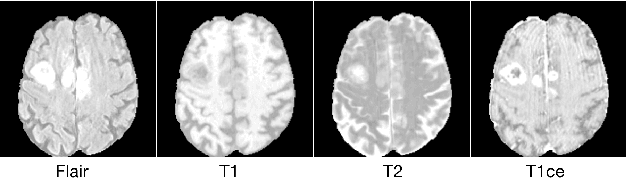

Precise segmentation of a lesion area is important for optimizing its treatment. Deep learning makes it possible to detect and segment a lesion field using annotated data. However, obtaining precisely annotated data is very challenging in the medical domain. Moreover, labeling uncertainty and imprecision make segmentation results unreliable. In this paper, we address the uncertain boundary problem by a new evidential neural network with an information fusion strategy, and the scarcity of annotated data by semi-supervised learning. Experimental results show that our proposal has better performance than state-of-the-art methods.